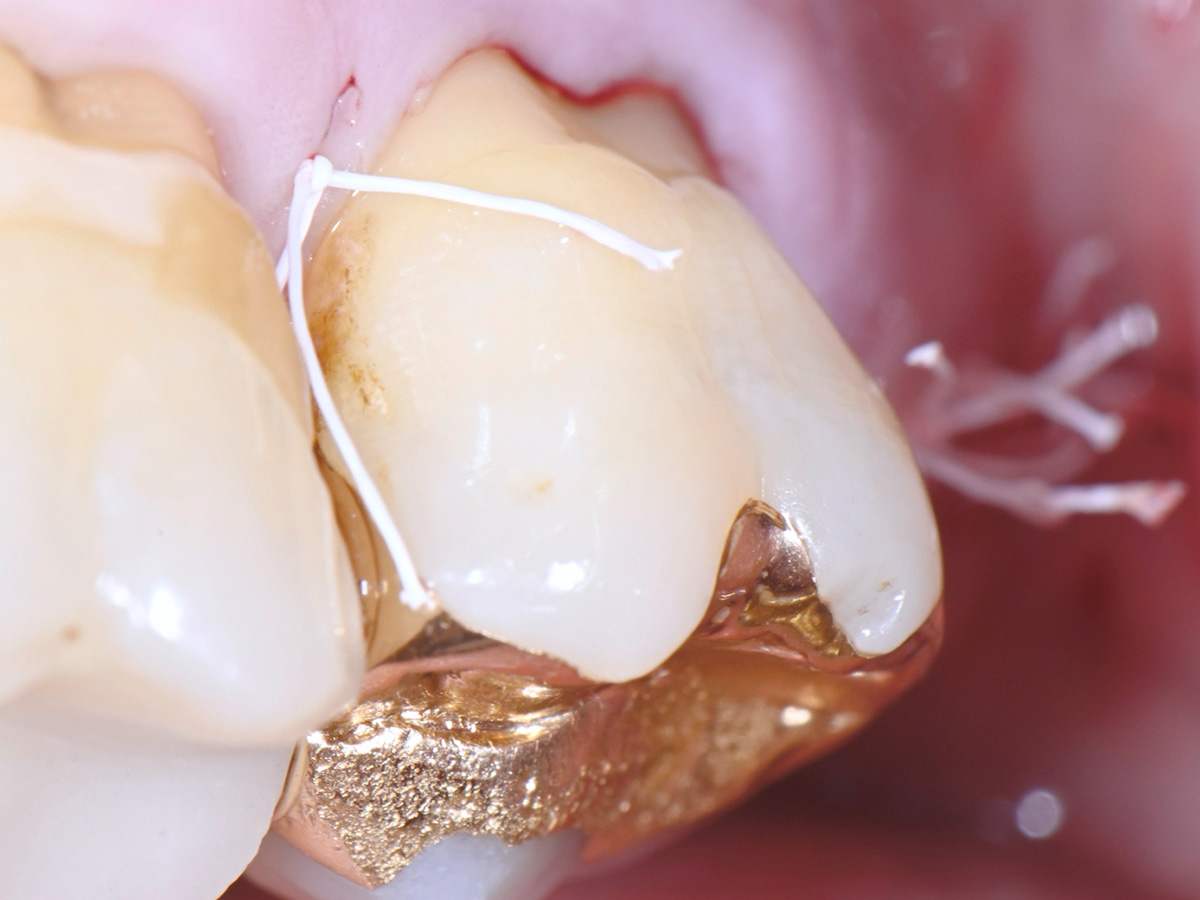

Abbildung 12

Nahtverschluss nach Entnahme mit der Keydent PTFE 4-0 Dental Suture